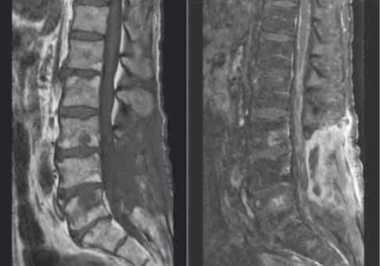

69 yaşında erkek hasta acil servise 2 aydır ilerleyici şekilde devam eden bilateral alt ekstremite güç kaybı, sol fasiyal güçsüzlük, diplopi, son 6 ayda 20,4 kg kayıp ve yeni başlangıçlı üriner inkontinans yakınmaları ile başvuruyor. Yakınmalarından 2 ay önce semptomatik spinal stenoz nedeniyle 3 lumbar ve 1 sakral vertebrayı içerecek şekilde laminektomi operasyonu geçirmiş. Ancak, cerrahiden fayda görmediğini, bacaklarındaki kuvvetsizliğin arttığını belirtiyor. Baş ağrısı, ateş, öksürük, immünosüpresif ilaç kullanımı, yurtdışı seyahat öyküsü tariflemiyor. Özgeçmişinde, hipertansiyon ve 50 paket/yıl sigara içme öyküsü var. Vital bulguları stabil olan hastanın nörolojik muayenesinde bilinci açık, solda görme keskinliği 20/400, solda afferent pupil defekti, solda fasiyal paralizi saptanıyor. Tüm ekstremitelerinde kas kütlesinde azalma ve hipotoni dikkati çekiyor. Üst torakal bölgede ve bilateral alt ekstremitelerde fasikülasyon gözleniyor. Alt ekstremitelerde kas gücü 2/5 saptanıyor, DTR alınamıyor. Duyu muayenesinde anormallik saptanmıyor. Laboratuvar tetkiklerinde tam kan sayımı, PAAC grafisi ve akciğer tomografisi normal saptanıyor. Kontrastlı kranial ve spinal MRG’de serebral konveksitelerde, serebellumda, kauda ekuina dahil spinal kord leptomeninkslerinde kontrast tutulumu gözleniyor (Şekil).  BOS incelemesinde hemen tamamı lenfosit hakiminde olmak üzere beyaz küre 29/mm3, protein 142 mg/dL, glukoz 19 mg/dL saptanıyor. BOS sitolojisi normal saptanan hastanın, tüberküloz ve mantar enfeksiyon incelemeleri de negatif bulunuyor. Tekrarlanan akım sitometride anormal B ve T hücre popülasyonu gözlenmiyor. Serum ACE’si normal saptanıyor. Tüm vücut PET incelemesine yoğun leptomemingeal ve sinir kökü hipermetabolizması saptansa da, primer malignansiye ait kanıt bulunamıyor. Bu hastanın en olası tanısı nedir?

Doğru yanıt A şıkkıdır. Hasta subakut, progresif, kranial nöropati, lumbosakral radikülopati klinik tablosu, multifokal leptomemingeal kontrast tutulumu gösteren görüntüleme tetkiki ve BOS’ta glukoz düşüklüğüne eşlik eden lenfositik pleositoz tablosu ile başvuruyor. Bu hastada en olası tanı SSS lenfoma varyantıdır. Ayırıcı tanıda düşünülecek nörosarkoidoz, hastanın bilgilerinde verilmeyen lenfadenopati, görüntülemelerde bahsedilmeyen granülom ve ACE negatifliği ile dışlanıyor.